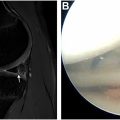

Restoration of ROM to preoperative values and focus on total arc of motion are critical to prevent high torque on the shoulder and elbow during throwing. It is important to note that overhead athletes, and particularly pitchers, have different ROM profiles when comparing the dominant to the nondominant arm. Pitchers have decreases in dominant elbow extension (7.9°), elbow flexion (5.5°), and total flexion-extension arc (13.3°) when compared to the nondominant arm. , When looking at pitchers’ passive dominant shoulder ROM, they demonstrate on average 132° of external rotation (ER) at 90°, 52° of internal rotation (IR), and 102° of mean ER at 45° of abduction. These values can be used as a baseline when examining either ROM deficits or excesses. A shoulder flexion deficit greater than 5° is a significant risk factor for elbow injury, and the risk of elbow injury increases by 7% for each degree of ER deficit and 9% for each degree of decreased shoulder flexion. The loss of shoulder rotational ROM and increased elbow flexion can increase shoulder and elbow torque and risk for reinjury. However, too much shoulder ER can also predispose players to injuries, and therefore, a balance must be struck. Prioritizing postoperative matching of preoperative ROM rather than emphasizing end range stretching should be the focus during rehabilitation, which has been shown to improve outcomes during rehabilitation.

Previously, much of the focus on ROM was on glenohumeral internal rotation deficits (GIRDs); however, recent literature suggests that the focus should instead be shifted to rotational motion (total arc of motion). Certainly baseball pitching prior to skeletal maturity does contribute to an increased humeral retrotorsion, which is then reflected in an increased external and decreased internal rotation, without a change in total rotational arc. It has been shown that a decreased total arc of motion is significantly associated with IR deficits and, therefore, represents the underlying cause of GIRDs. Additionally, decreased total arc of motion is associated with decreased shoulder strength. Furthermore, a decrease in rotator cuff stiffness is associated with acute ROM gains as opposed to glenohumeral joint mobility or humeral torsion. Baseball players with shoulder pain show a significant decrease in total arc of shoulder motion, along with IR compared to pain-free players. ROM exercises should, therefore, focus on restoring total arc of motion rather than solely IR deficits, which will ultimately lead to improved strength and decreased rotator cuff stiffness that lead to decreased pain and risk of reinjury.